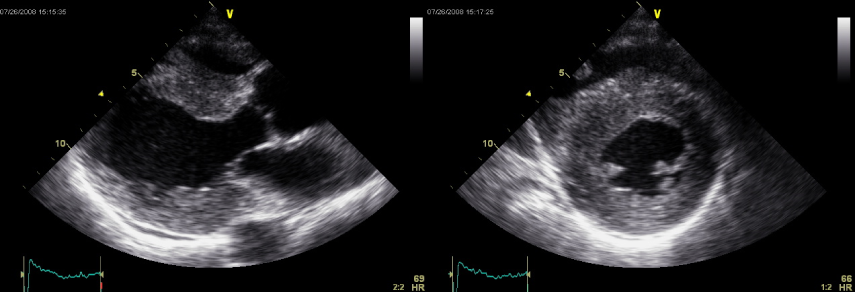

ALアミロイドーシス患者の左心耳内にできた血栓像

左心耳は血栓の好発部位で、経食道エコー以外に経胸壁心エコーでも血栓を検出できる場合がある。